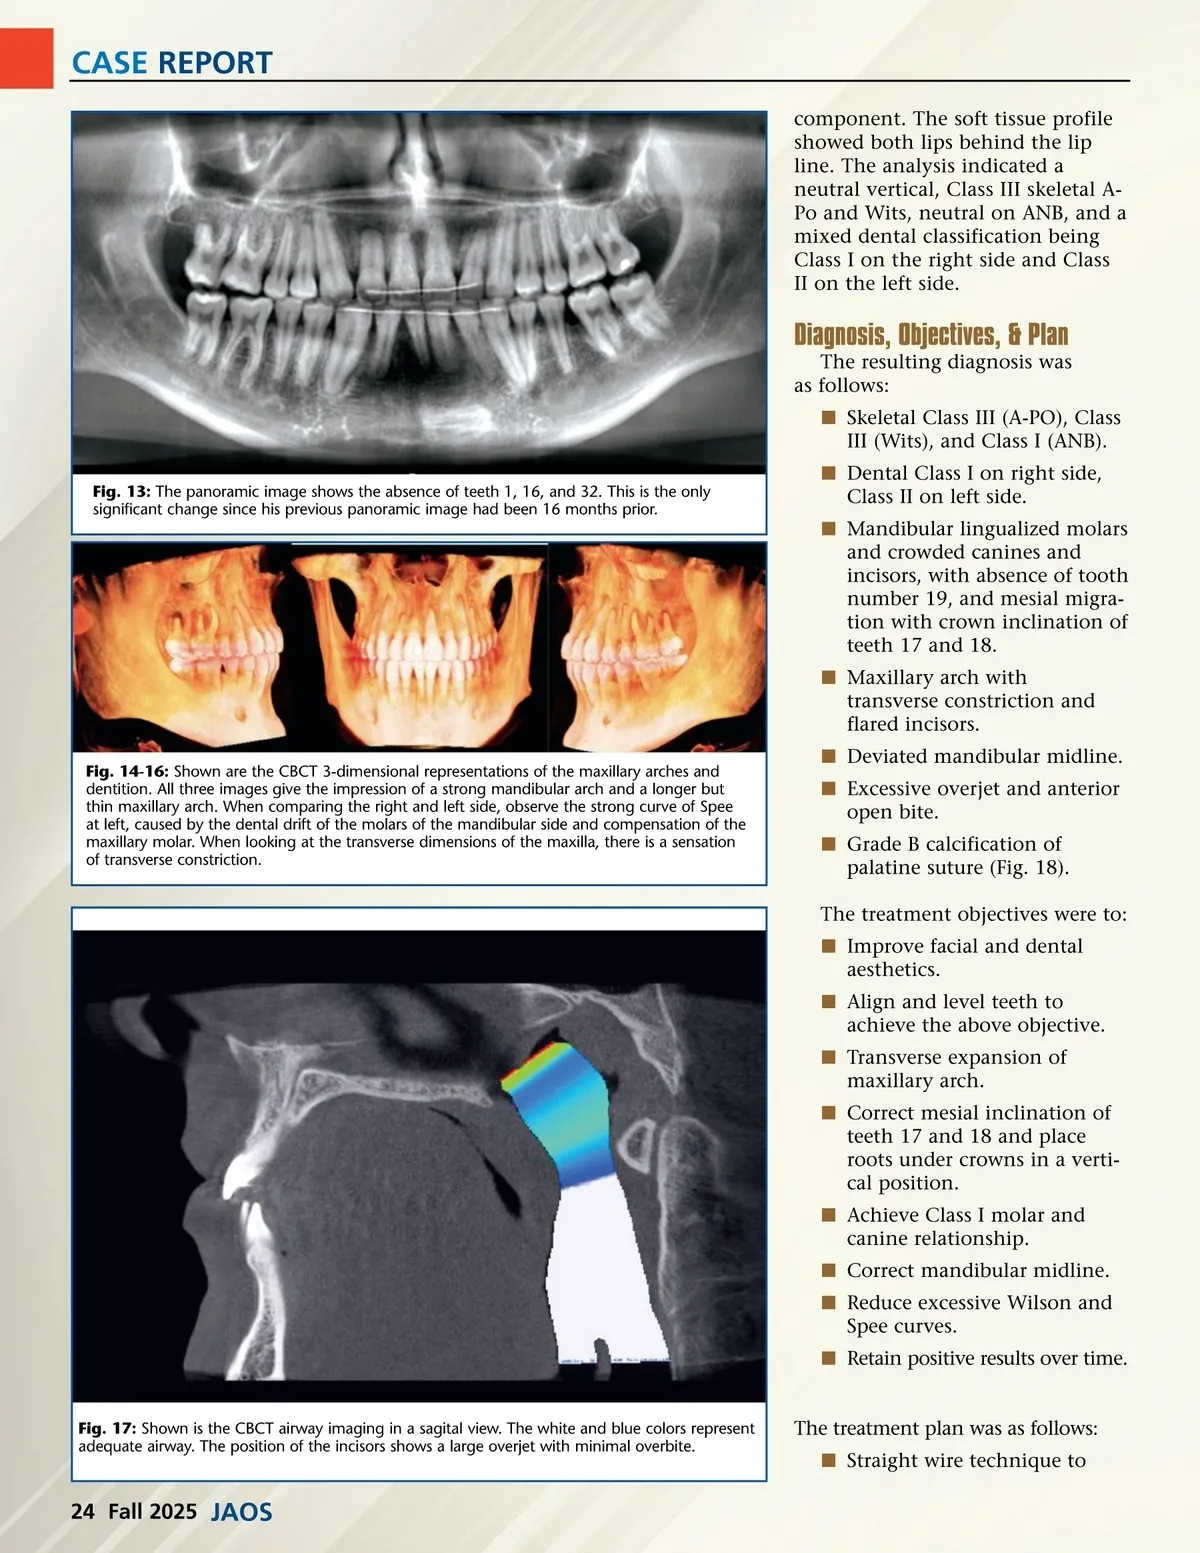

CASE REPORT component. The soft tissue profile showed both lips behind the lip line. The analysis indicated a neutral vertical, Class III skeletal A-Po and Wits, neutral on ANB, and a mixed dental classification being Class I on the right side and Class II on the left side. Diagnosis, Objectives, & Plan The resulting diagnosis was as follows: í Skeletal Class III (A-PO), Class III (Wits), and Class I (ANB). Fig. 13: The panoramic image shows the absence of teeth 1, 16, and 32. This is the only significant change since his previous panoramic image had been 16 months prior. í Dental Class I on right side, Class II on left side. í Mandibular lingualized molars and crowded canines and incisors, with absence of tooth number 19, and mesial migra-tion with crown inclination of teeth 17 and 18. í Maxillary arch with transverse constriction and flared incisors. Fig. 14-16: Shown are the CBCT 3-dimensional representations of the maxillary arches and dentition. All three images give the impression of a strong mandibular arch and a longer but thin maxillary arch. When comparing the right and left side, observe the strong curve of Spee at left, caused by the dental drift of the molars of the mandibular side and compensation of the maxillary molar. When looking at the transverse dimensions of the maxilla, there is a sensation of transverse constriction. í Deviated mandibular midline. í Excessive overjet and anterior open bite. í Grade B calcification of palatine suture (Fig. 18). The treatment objectives were to: í Improve facial and dental aesthetics. í Align and level teeth to achieve the above objective. í Transverse expansion of maxillary arch. í Correct mesial inclination of teeth 17 and 18 and place roots under crowns in a verti-cal position. í Achieve Class I molar and canine relationship. í Correct mandibular midline. í Reduce excessive Wilson and Spee curves. í Retain positive results over time. The treatment plan was as follows: í Straight wire technique to Fig. 17: Shown is the CBCT airway imaging in a sagital view. The white and blue colors represent adequate airway. The position of the incisors shows a large overjet with minimal overbite. 24 Fall 2025 JAOS